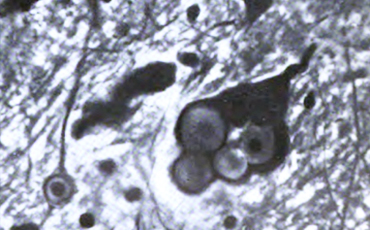

Durante su estancia en Washington, estudió en 1911 un caso de epilepsia mioclónica familiar, describiendo el cuadro clínico del proceso, el carácter hereditario autosómico recesivo y el hallazgo de inclusiones de cuerpos amiláceos en las neuronas, formulando la hipótesis de que la enfermedad era un trastorno metabólico congénito. Publicó este caso en Alemania, y amplió su estudio en colaboración con Glueck.

La enfermedad de Lafora es un cuadro neurológico que se inicia en la segunda década de la vida, es de carácter hereditario de forma autosómica recesiva. Clínicamente se caracteriza por la presentación de mioclonías, crisis parciales del lóbulo occipital, crisis generalizadas y demencia progresiva. La enfermedad ocasiona la muerte en pocos años de evolución. El diagnóstico puede confirmarse por biopsia cutánea, en zonas con presencia de glándulas apocrinas, como la región axilar. La presencia de cuerpos de Lafora es determianante para el diagnóstico. Los cuerpos de Lafora consisten en acúmulo de glicógeno anormal, con cadenas periféricas lineales muy largas. Cerca del 80 % de casos son debidos a una mutación en el gen EPM2 que codifica una fosfatasa que es laforina. El gen NHLCRC1 codifica la malina, una E3 ubicuitina ligasa, que determina la degradación de laforina. El diagnóstico patológico se realiza por la presencia de la inclusión de los llamados cuerpos de Lafora en el cerebro, músculos, hígado y piel.